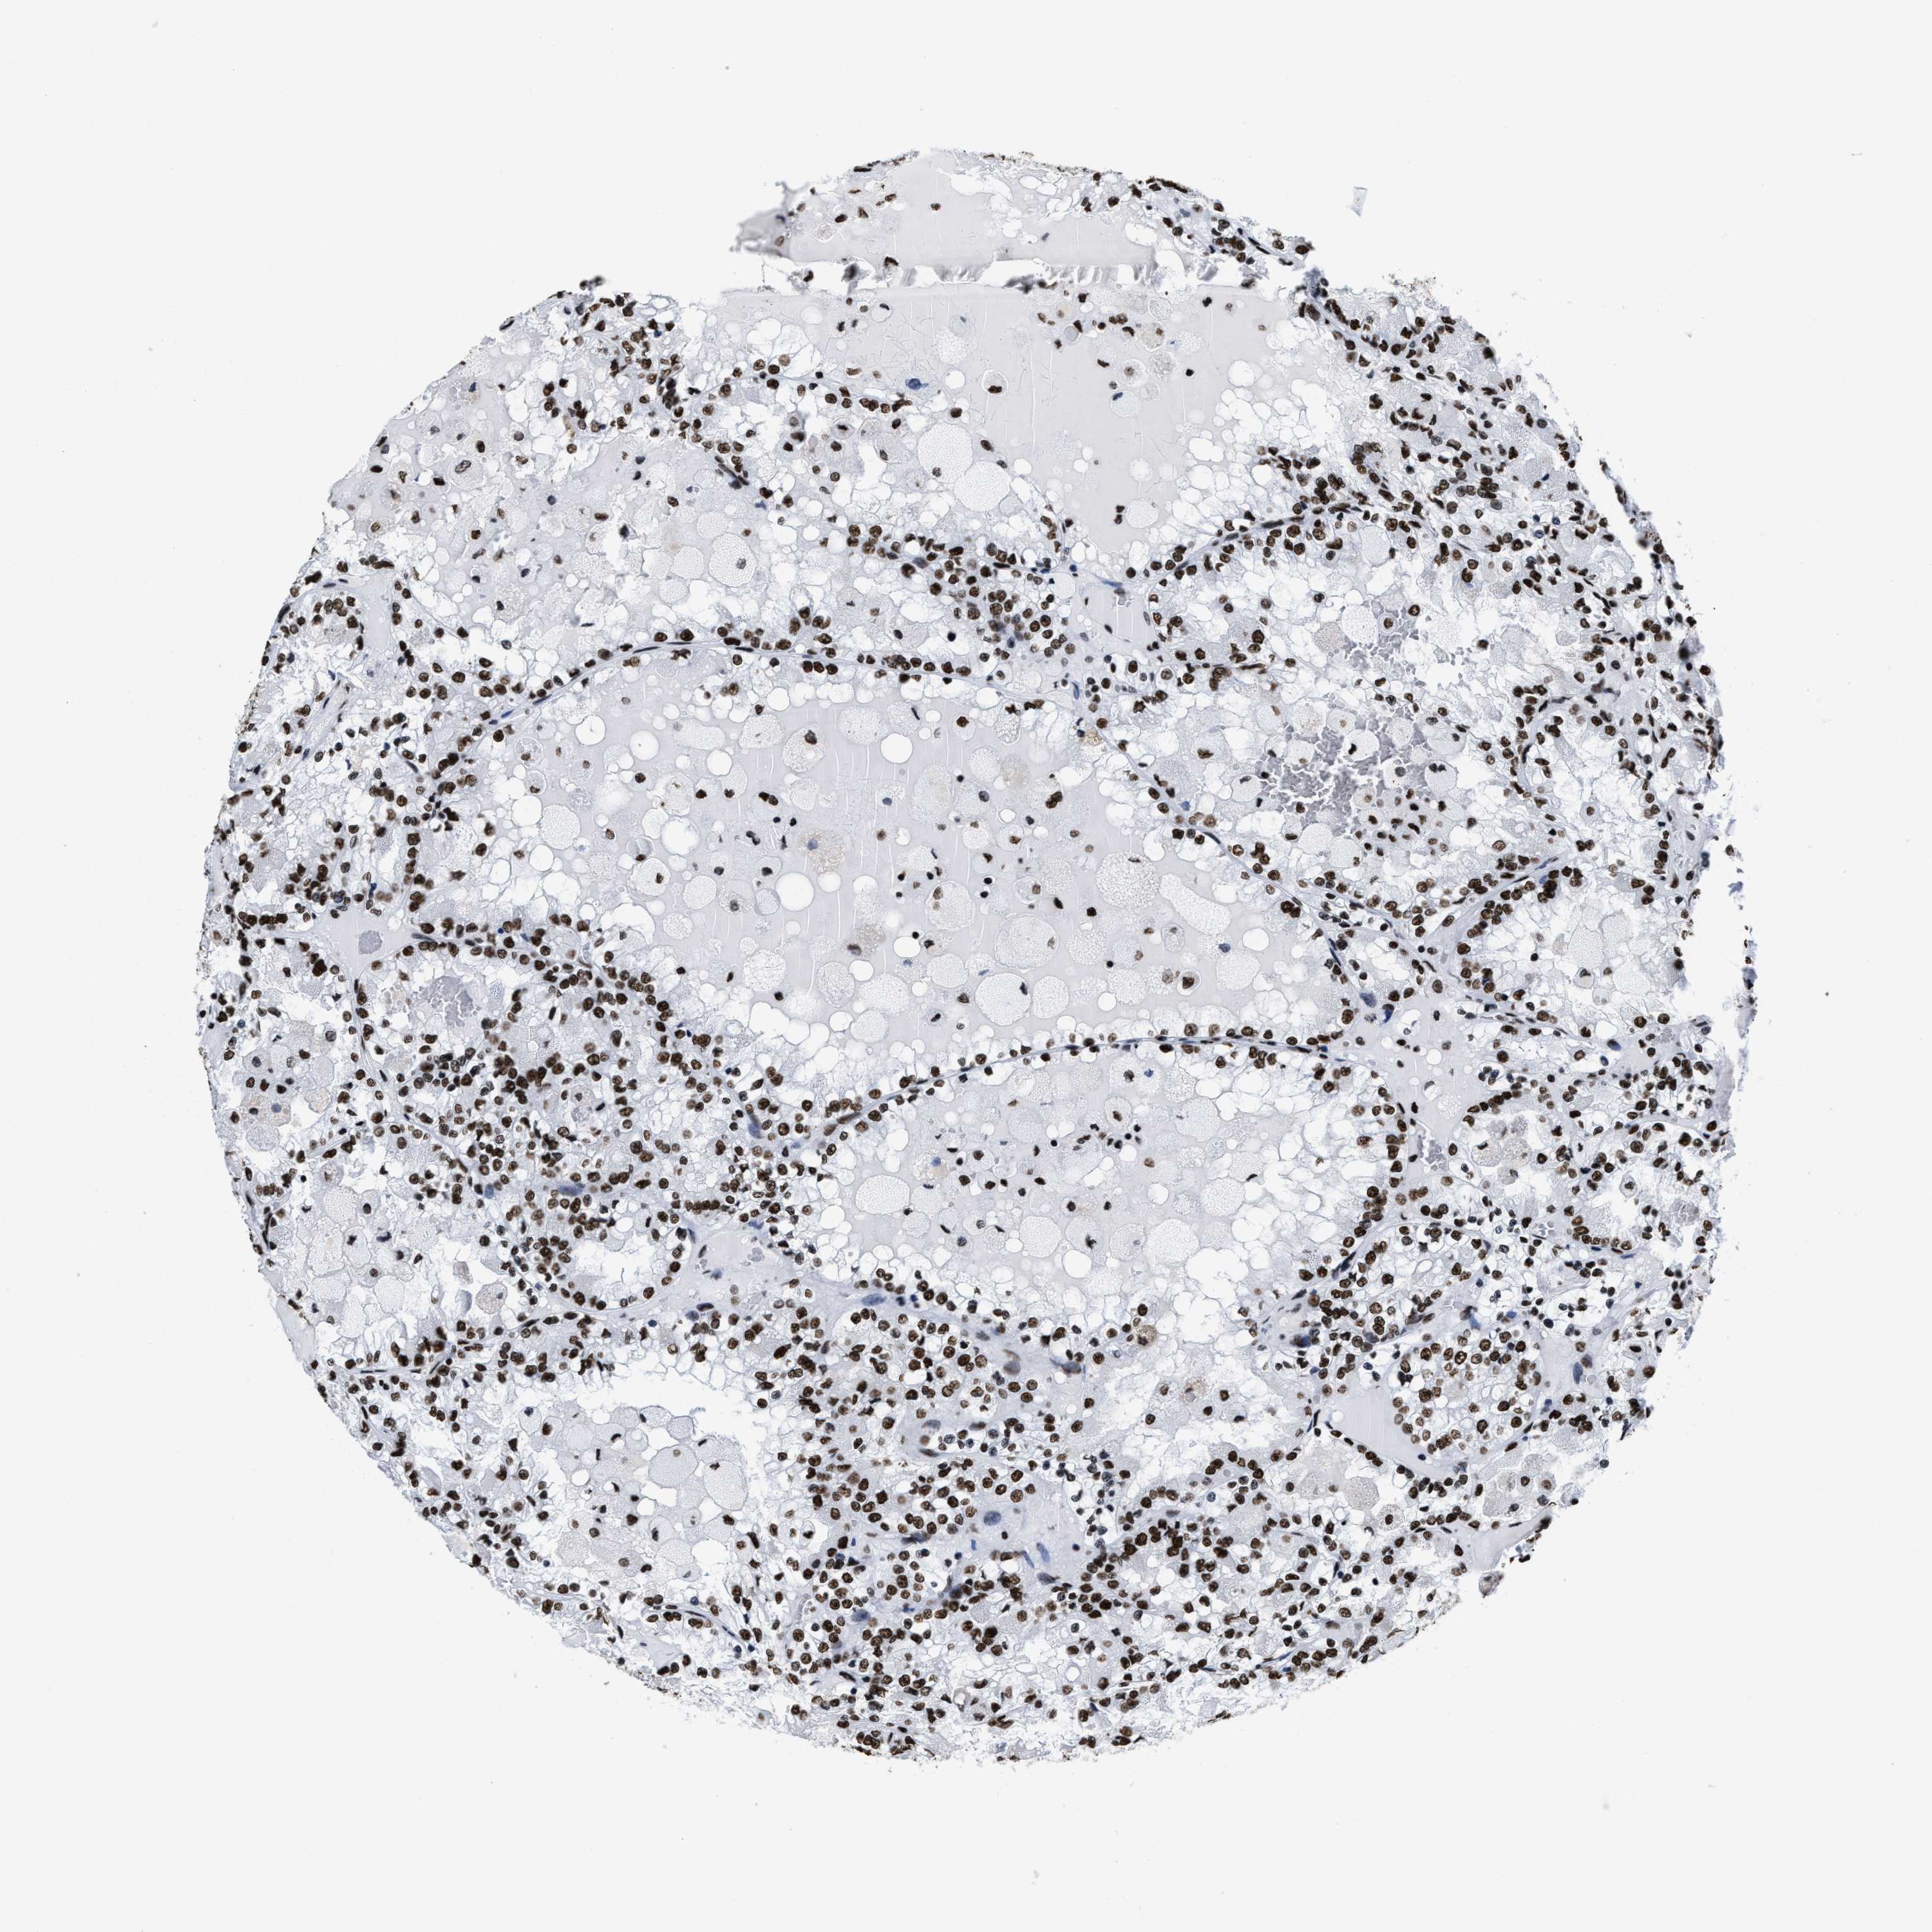

KIDNEY RENAL CLEAR CELL CARCINOMA (TCGA) - Interactive survival scatter ploti

The Survival Scatter plot shows the clinical status (i.e. dead or alive) for all individuals in the patient cohort, based on the same data that underlies the corresponding Kaplan-Meier plots. Patients that are alive at last time for follow-up are shown in blue and patients who have died during the study are shown in red.

The x-axis shows the expression levels (FPKM) of the investigated gene in the tumor tissue at the time of diagnosis. The y-axis shows the follow-up time after diagnosis (years). Both axes are complimented with kernel density curves demonstrating the data density over the axes. The top density plot shows the expression levels (FPKM) distribution among dead (red) and alive patients (blue). The right density plot shows the data density of the survived years of dead patients with high and low expression levels respectively, stratified using the cutoff indicated by the vertical dashed line through the Survival Scatter plot. This cutoff is automatically defined based on the FPKM cutoff that minimizes the p-score. The cutoff can be changed by dragging the vertical line or by entering a cutoff value in the square labeled "Current cut-off".

Under the Survival Scatter plot the p-score landscape (black curve; left axis) is shown together with dead median separation (red curve; right axis). Dead median separation is the difference in median mRNA expression between patients who have died with high and low expression, respectively. It is calculated as follows: median FPKM expression of dead patients with high expression - median FPKM expression of dead patients with low expression. This is intended to aid the user in visually exploring custom cutoffs and the associated p-scores and dead median separation.

Individual patient data is displayed and can be filtered by clicking on one or more of the category buttons on the top of the page. Categories describing expression level and patient information include: high, low, alive, dead, female, male and tumor stages. The scale of the x-axis can be toggled between linear and log-scale by clicking on the "x log" button. Mouse-over function shows TCGA ID, patient information and mRNA expression (FPKM) for each patient.

& Survival analysisi

Kaplan-Meier plots summarize results from analysis of correlation between mRNA expression level and patient survival. Patients were divided based on level of expression into one of the two groups "low" (under cut off) or "high" (over cut off). X-axis shows time for survival (years) and y-axis shows the probability of survival, where 1.0 corresponds to 100 percent.

SMARCC2 is not prognostic in Kidney Renal Clear Cell Carcinoma (TCGA)

Best expression cut offi

Based on the FPKM value of each gene, patients were classified into two groups and association between prognosis (survival) and gene expression (FPKM) was examined. The best expression cut-off refers the FPKM value that yields maximal difference with regard to survival between the two groups at the lowest log-rank P-value. Best expression cut-off was selected based on survival analysis .

When clicking on this number, the vertical dashed line indicating cut-off, the interactive survival plot, and the Kaplan-Meier curve will be adjusted to show results based on the best expression cut-off.

: 32.12

Median expressioni

Median expression refers to the median FPKM value calculated based on the gene expression (FPKM) data from all patients in this dataset. When clicking on this number, the vertical dashed line indicating cut-off, the interactive survival plot, and the Kaplan-Meier curve will be adjusted to show results based on the median expression.

: N/A

Median follow up timei

Median follow up time refers to the median time (years) after diagnosis with this type of cancer, based on clinical data from all patients in this dataset.

P scorei

Log-rank P value for Kaplan-Meier plot showing results from analysis of correlation between mRNA expression level and patient survival.

N/A

5-year survival highi

5-year survival for patients with higher expression than the expression cutoff.

For melanoma and glioma, 3-year survival is shown.

5-year survival lowi

5-year survival for patients with lower expression than the expression cutoff.

TCGA RNA samplesi

RNA-seq data is reported as average FPKM (number Fragments Per Kilobase of exon per Million reads), generated by the The Cancer Genome Atlas (TCGA) .

Normal distribution across the dataset is visualized with box plots, shown as median and 25th and 75th percentiles. Points are displayed as outliers if they are above or below 1.5 times the interquartile range. FPKM values of the individual samples are presented next to the box plot.

Average pTPM 35.4

Number of samples 521